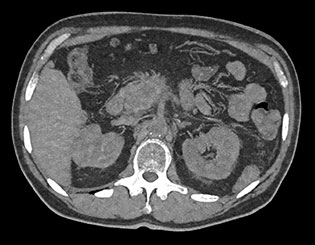

Здесь представлена серия изображений, на которых значения воксела обозначают эффективное атомное число. Эффективное атомное число может быть дробным, обозначающим какой-либо элемент, соединение или смесь. Данное число может отличаться от порядкового номера, указанного в периодической таблице. Единица для обозначения — Z.